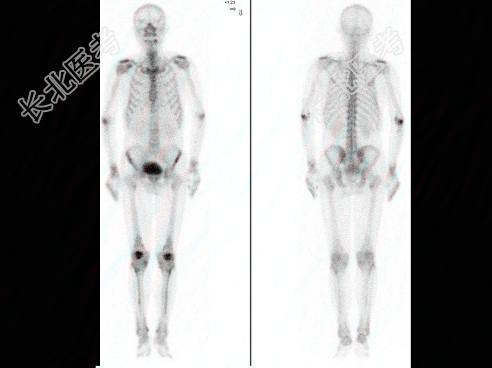

- 多项选择题男,69岁, 肺癌化疗中,诉下肢疼痛3个月, 行全身骨显像如图,可能的诊断 ( )

A、双侧膝关节转移瘤

B、双侧胫骨转移瘤

C、双下肢肥大性骨关节病

D、未见骨转移征象

E、有“热髌征”